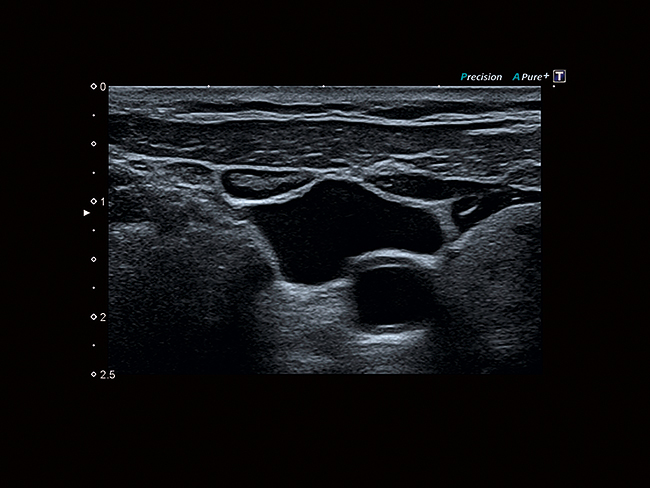

Глубина и детализация

Дифференциальная гармоническая визуализация тканей (D-THI) обеспечивает изображения с непревзойденным пространственным разрешением и контрастностью.